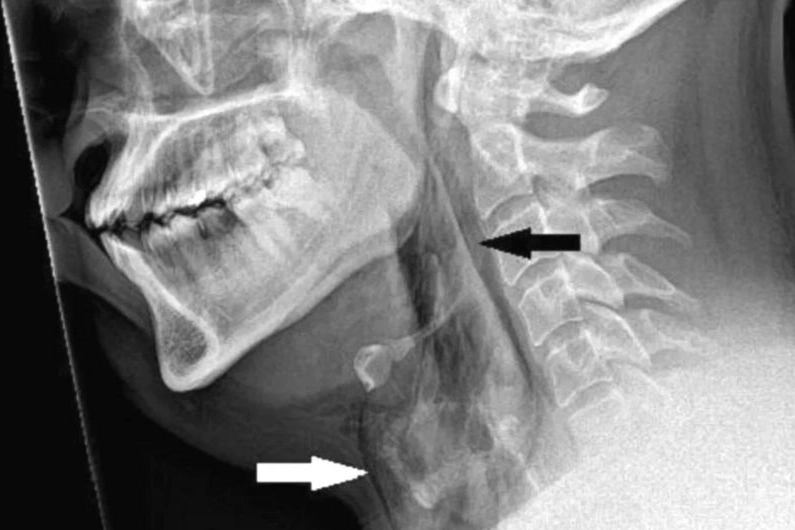

Yapılan taramalarda hastanın nefes borusunda 2 milimetrelik bir yırtık olduğu ortaya çıktı.

Doktorlar hastayı muayene için boynuna dokunduklarında bir çıtırtı sesi duymuş ve hastanın hareket kontrolünün olmadığını tespit etmişti.

Raporu hazırlayan Dr. Rasads Misirovs, "Burnu sıkışık ve ağzı kapalı bir şekilde hapşırırken soluk borusunda hızlı bir şekilde basınç oluşması nedeniyle soluk borusunun yırtıldığından şüpheleniyoruz" dedi ve bu risk nedeniyle, ağzı ve burnu kapatarak, hapşırmanın bastırılmaması konusunda uyardı.

Tıbbi adıyla "spontane trakeal perforasyon" olarak bilinen ani boğaz yırtılması nadir görülse de potansiyel olarak hayati tehlikeye yol açabilir.